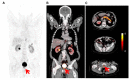

Metastatic castration-resistant prostate cancer (mCRPC) represents a condition of progressive disease in spite of androgen deprivation therapy (ADT), with a broad spectrum of manifestations ranging from no symptoms to severe debilitation due to bone or visceral metastatization. The management of mCRPC has been profoundly modified by introducing novel therapeutic tools such as antiandrogen drugs (i.e., abiraterone acetate and enzalutamide), immunotherapy through sipuleucel-T, and targeted alpha therapy (TAT). This variety of approaches calls for unmet need of biomarkers suitable for patients' pre-treatment selection and prognostic stratification. In this scenario, imaging with positron emission computed tomography (PET/CT) presents great and still unexplored potential to detect specific molecular and metabolic signatures, some of whom, such as the prostate specific membrane antigen (PSMA), can also be exploited as therapeutic targets, thus combining diagnosis and therapy in the so-called "theranostic" approach. In this review, we performed a web-based and desktop literature research to investigate the prognostic and theranostic potential of several PET imaging probes, such as 18F-FDG, 18F-choline and 68Ga-PSMA-11, also covering the emerging tracers still in a pre-clinical phase (e.g., PARP-inhibitors' analogs and the radioligands binding to gastrin releasing peptide receptors/GRPR), highlighting their potential for defining personalized care pathways in mCRPC.